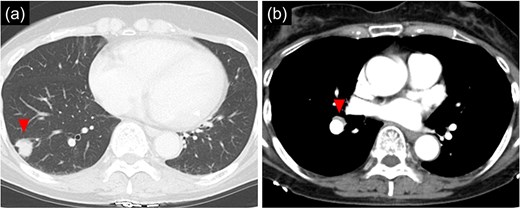

The patient was a 66 year-old woman with no history of smoking or other medical history. Chest CT showed an 18 mm nodule suspected to be a primary lung cancer in the S9 region of the right lower lobe (Fig. 1). CT-guided lung biopsy revealed lung adenocarcinoma. PET/CT showed FDG accumulation in #11i lymph node suspicious for metastasis, and the preoperative staging was c-T1bN1M0 Stage IIB. The patient was referred to the Department of Thoracic Surgery in our hospital. In addition, a 9 mm size BD communicating with the right main bronchus was observed below the tracheal bifurcation in the preoperative image (Fig. 2). Right lower lobectomy and mediastinal lymph node dissection were planned; however, because the inferior mediastinal tissue was to be dissected, a procedure for BD was also considered necessary. To achieve safe dissection around the BD, robotic thoracoscopic surgery was planned, taking advantage of the fine movement and highly flexible forceps manipulation.

Chest computed tomographic image. (a) An 18 mm size nodule is detected in the S9 region of the right lower lobe. (b) An enlarged lymph node (#11iLN) with fluorodeoxyglucose accumulation is located anterior to the basal segment of the pulmonary artery.